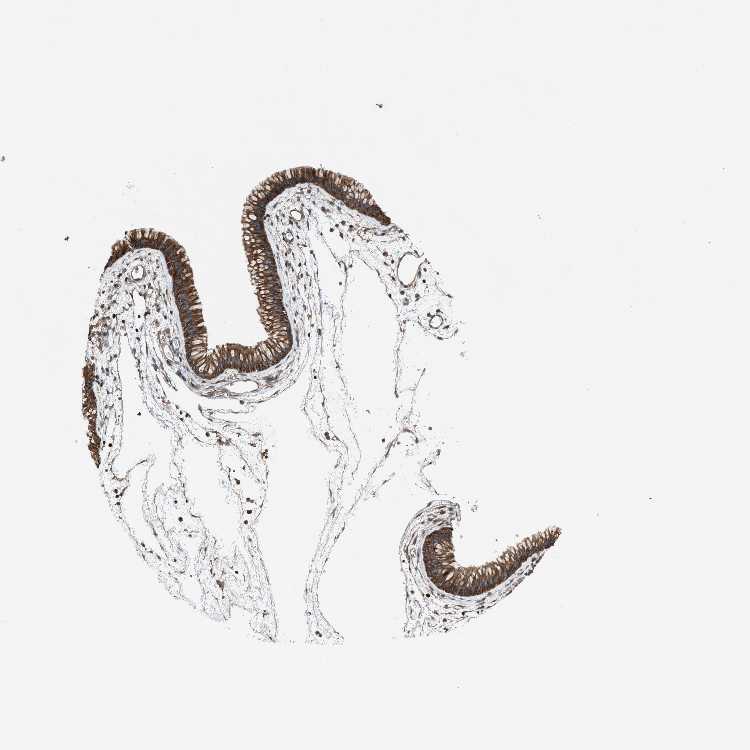

TISSUE PRIMARY DATA NASOPHARYNX Show tissue menu

NASOPHARYNX - Antibody stainingi

Antibody staining in the annotated cell types in the current human tissue is reported as not detected, low, medium, or high, based on conventional immunohistochemistry profiling in selected tissues. This score is based on the combination of the staining intensity and fraction of stained cells.

Each image is clickable and will lead to virtual microscopy that enables deeper exploration of all samples and also displays staining intensity scores, fraction scores and subcellular localization as well as patient and tissue information for each sample.

Antibody HPA015323Antibody HPA015810

Respiratory epithelial cells HighMedium